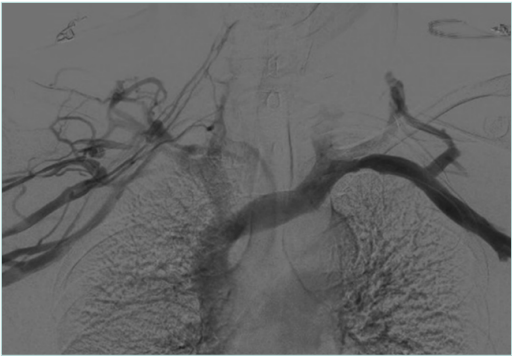

Figure 3. Venogram of arms in neutral position with postthrombotic syndrome (PTS) on the right side and no venographic signs of venous obstruction on the left side.

Figure 4. Venogram for arms in abduction position showing subclavian vein compression on both sides.